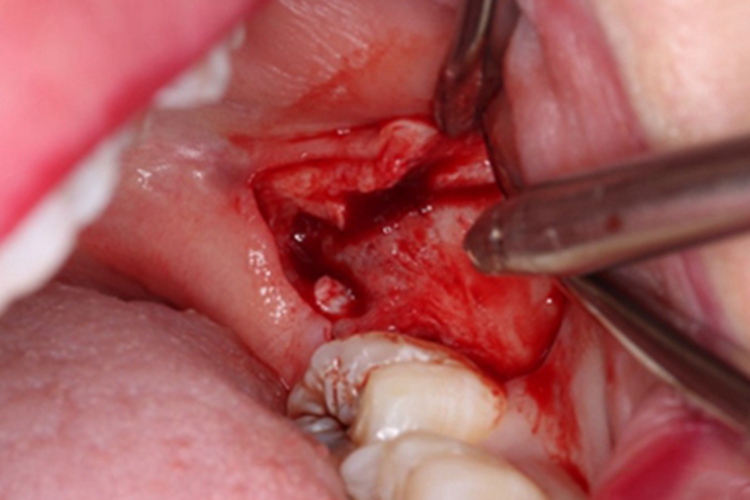

切开及翻瓣

拔牙前应彻底冲洗盲袋,切开翻瓣后还应进一步冲洗。水平阻生智齿一般完全不萌出,需作远中切口及颊侧切口,然后用薄的骨膜分离器直抵骨面,紧贴骨面向后向颊侧将瓣掀开。